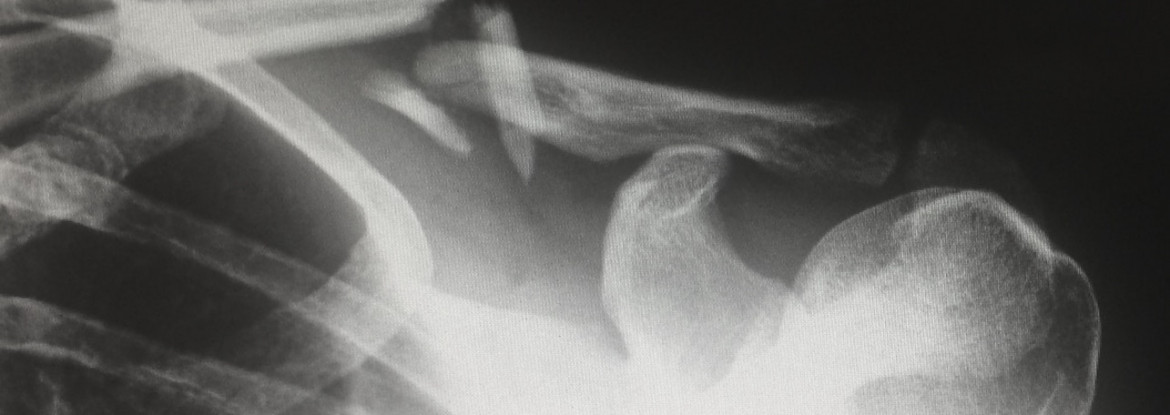

通用射线照相使用X射线来产生体内内部的详细图像。X射线机产生穿过身体的X射线以产生图像。它采用了医学摄影,其中快照由指定的身体部位制成。

在检查过程中,病人被定位,使被成像的身体部分位于受体和x光管之间。常见的x线检查包括四肢(手,脚)和胸部的成像。虽然x光对骨骼最好,但它可以看到许多软组织结构。